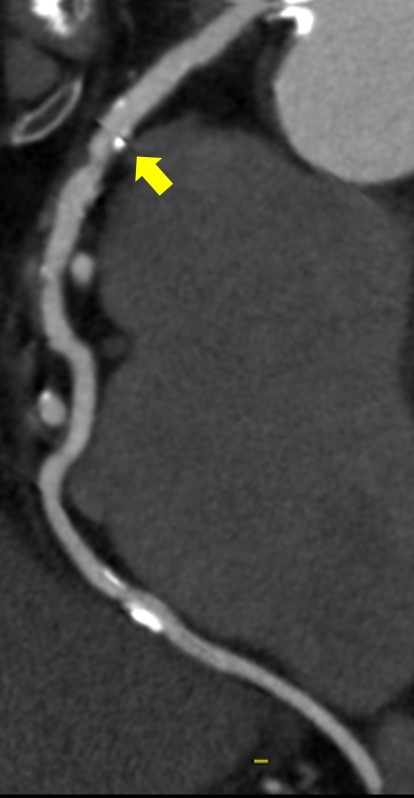

下記の画像は、TAVI術前検査のAf症例ですが、このデータでも不整脈や石灰化があるにも関わらず弁に対して十分な画像が得られており、列数の影響を感じさせない画像が提供することができました。

循環器医師からも、「64列装置でも十分評価できているね!」と言っていただけるほど、評価が高かったことが印象的です。

Ascend_ayase04.jpgTAVI術前検査でのSSF2.0処理後の画像